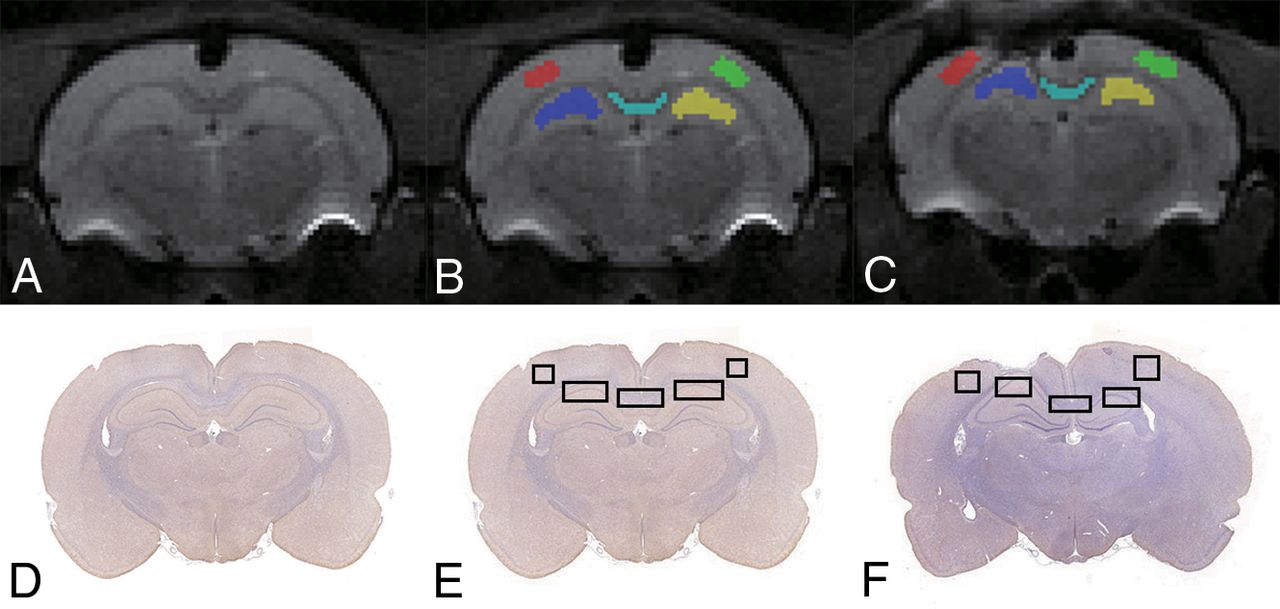

Diffusional Kurtosis Estimator software was used to calculate the DKI parameters (https://www.nitrc.org/projects/dke/).22 The calculated DKI parameters included MK, axial kurtosis (Ka), and radial kurtosis (Kr); FA, MD, axial diffusion (Da); and radial diffusion (Dr). Using ITK-SNAP software (www.itksnap.org),23 we manually drew multiple ROIs, including ipsilateral and contralateral to the injury in the cortex, hippocampus, and corpus callosum (Fig 1) on the b=0 image at around 3–4 mm posterior to bregma. These ROIs were selected because they were all possibly related to cognitive impairment in the TBI animal model.24,25 The individual drawing the ROI was trained before analysis of the study data. The ROIs should be sufficiently large but not defined to the edge of the tissues on the section. A single voxel width was used for the delineation of corpus callosum. Then, the ROIs were transferred to identical sites on the FA, MD, Da, Dr, MK, Ka, and Kr maps in the same rat. The average regional value for each DKI parameter was recorded from the voxels within each ROI.

Illustration of ROIs on B0 (A–C) and histology (D–F) maps for a representative control and TBI rat. Regions shown are the bilateral cortex, bilateral hippocampus, and corpus callosum.

Brain IHC images were captured using a microscope for cell counting of NeuN+, GFAP+, and Iba-1+ cells and the IHC staining area of MBP. Three random FOVs of each section at a magnification of ×20 were obtained to quantify the IHC result to match the MR imaging measured area (Fig 1). The mean values were used to indicate the positive cell numbers or area percentage in each region. Quantification of positive stained cells or area was performed manually using a computer-based image analysis system (Image J 1.51; National Institutes of Health, Bethesda, Maryland).